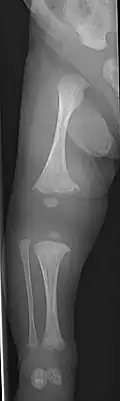

The main symptom of osteogenesis imperfecta is fragile, low mineral density bones; all types of OI have some bone involvement.[5] In moderate and especially severe OI, the long bones may be bowed, sometimes extremely so.[28] The weakness of the bones causes them to fracture easily—a study at the Endocrine Unit at the National Institute of Child Health in Karachi, Pakistan found an average of 5.8 fractures per year in untreated children.[29] Fractures typically occur much less after puberty, but begin to increase again in women after menopause and in men between the ages of 60 and 80.[1]: 486

Diagnosis is typically based on medical imaging, including plain X-rays, and symptoms. In severe OI, signs on medical imaging include abnormalities in all extremities and the spine.[97] As X-rays are often insensitive to the comparatively smaller bone density loss associated with type I OI, DEXA scans may be needed.[5]: 1514

An OI diagnosis can be confirmed through DNA or collagen protein analysis, but in many cases, the occurrence of bone fractures with little trauma and the presence of other clinical features such as blue sclerae are sufficient for a diagnosis. A skin biopsy can be performed to determine the structure and quantity of type I collagen. While DNA testing can confirm the diagnosis, it cannot absolutely exclude it because not all mutations causing OI are yet known and/or tested for.[83]: 491–492 OI type II is often diagnosed by ultrasound during pregnancy, where already multiple fractures and other characteristic features may be visible. Relative to control, OI cortical bone shows increased porosity, canal diameter, and connectivity in micro-computed tomography.[98] OI can also be detected before birth by using an in vitro genetic testing technique such as amniocentresis.[99]